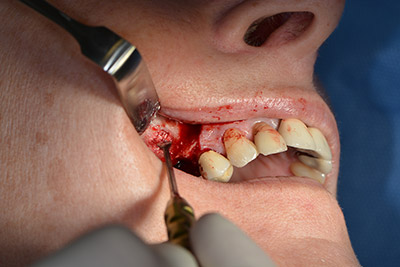

En el siguiente paso se efectúa la elevación del suelo del seno maxilar, a la vez que se coloca el implante. Para la fenestración lateral de la pared del seno maxilar Implantmed también cuenta con un ajuste predefinido en la primera posición.

La ventana se crea a una velocidad de 35.000 rpm y, a continuación, la membrana de Schneider se prepara en sentido craneal (figuras 13 a 14).